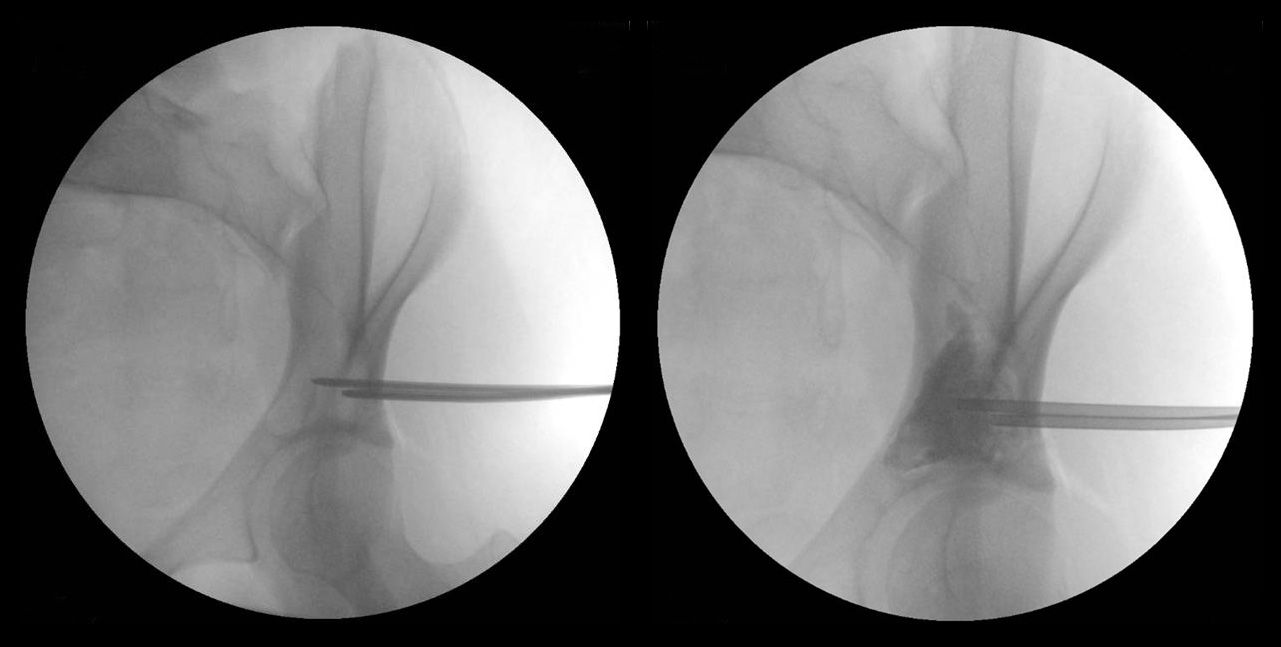

Aspiration of unicameral bone cyst

(Left) This X-ray taken in the operating room shows needles placed in the cyst for the aspiration. (Right) This X-ray shows the cyst after dye has been injected to help doctors make decisions about filling the cyst with materials to prevent recurrence.